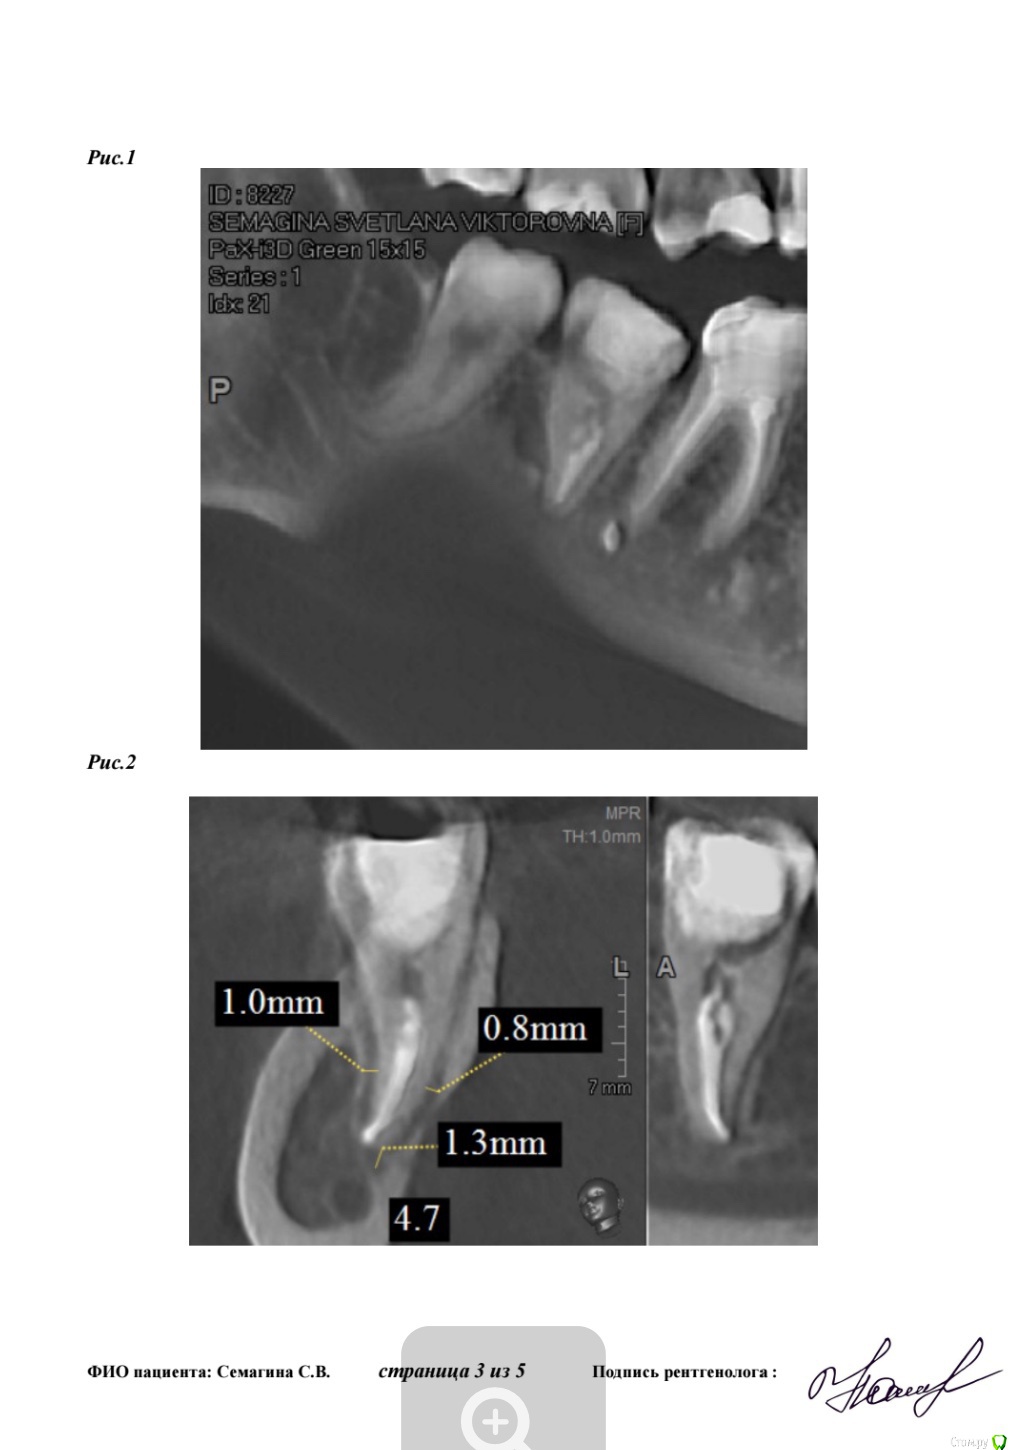

Лана-Лана Опубликовано 14 февраля, 2018 Поделиться Опубликовано 14 февраля, 2018 (изменено) Зуб семерка справа нижний, перелечивался после перидонтита... состояние такое как на кт, сам не болит но жевать невозможно, есть ли смысл перелечивать ? Очень хочу зуб сохранить... запломбированн на одну треть .. место под вкладку . На данный момент все таки раскрыли поставили метопасту. Изменено 14 февраля, 2018 пользователем Лана-Лана Ссылка на комментарий

Лана-Лана Опубликовано 15 февраля, 2018 Автор Поделиться Опубликовано 15 февраля, 2018 (изменено) Сейчас зуб в таком состоянии с метапиксом( перепутала изначально сказала метопаста), вижу темное пятно слева от зуба это что воспаление? И так же вижу слева как второй корень именно корень а не канал... он как бы чуть чуть выглядывает из за первого корня , или это наслоение какое то?. в первом корне 2 канала а может быть в другом корне тоже какой то патайной канал которого воачи не видят ? Изменено 15 февраля, 2018 пользователем Лана-Лана Ссылка на комментарий

Лана-Лана Опубликовано 17 февраля, 2018 Автор Поделиться Опубликовано 17 февраля, 2018 Зуб стал болеть с метапиксом такая давящая ноющая, припухлость не уходит! Что делать дальше? Ждать ? Сказали ходить три недели! Или пойти поменять лекарство? Уважаемые доктора посмотрите последний снимок почему лекарство не до апекса? Оно вообще как то подействует на воспаление в кости в десне? Может ли быть в таком зубе третий канал скрытый? Может какой то внутри разделяется на два? По кт может что то видно? Ссылка на комментарий